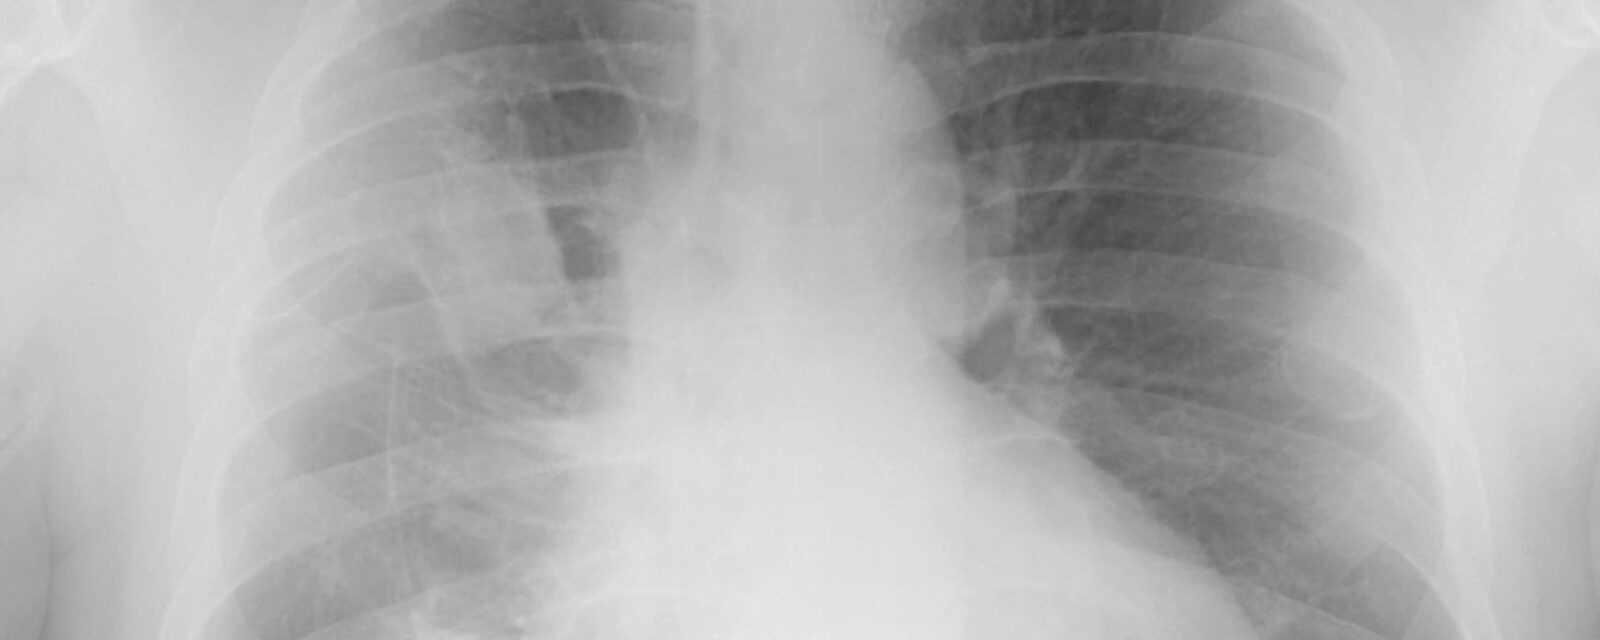

Digital x-ray image showing epithelioid mesothelioma cells.

You may find yourself undergoing several diagnostic procedures to confirm the presence of epithelioid mesothelioma cells. Most patients undergo imaging scans first to spot tumors, followed by a tissue biopsy that may find epithelial cells. Additional lab tests can be done to detect other characteristics of the cell type.